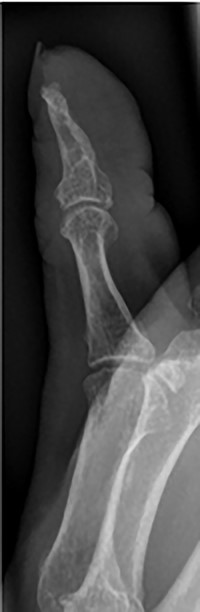

Her blood tests on presentation were unremarkable and X-rays of her right thumb showed a lytic lesion involving the tuft of the distal phalanx (Figs. 4 and 5). She was admitted to the hospital and was treated as having an infection of her right thumb with elevation and intravenous antibiotics. She underwent emergency surgery the next day for a washout and debridement of the right thumb. During the debridement in theatre, there was no pus in the pulp, but the bone was found to be eroded and soft, thus multiple specimens from the bone were sent for microscopy, culture and sensitivity, acid-fast bacilli (AFB) and histopathology.

AP radiograph of right thumb showing erosion of tip of distal phalanx.